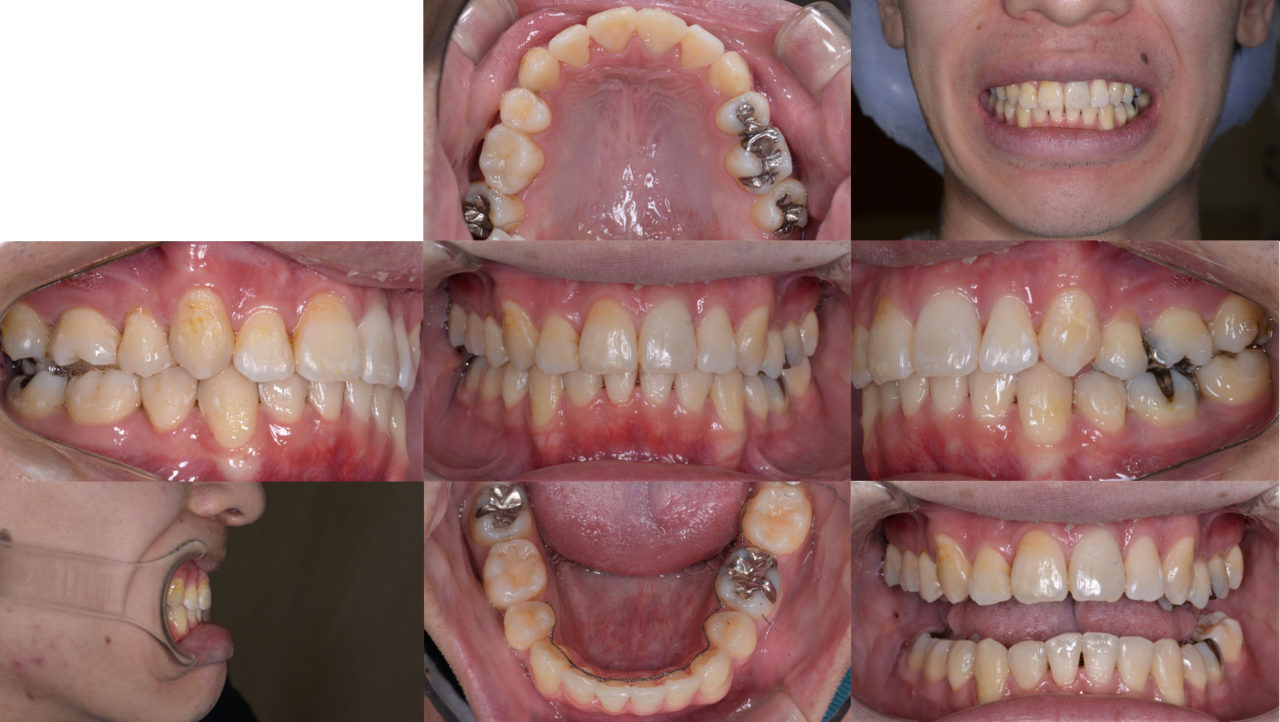

After

ファイナル 2019.12.6